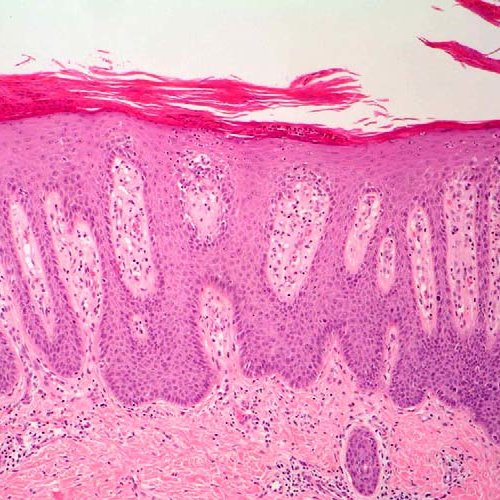

La lesión típica es una placa bien delimitada de color rosa-salmón revestida por una descamación blanquecino-plateada poco adherida. Existe un intenso engrosamiento de la epidermis (acantosis), con alargamiento regular hacia la parte inferior de las crestas papilares. El patrón de este creci miento hacia abajo se ha comparado con «tubos de ensayo en una gradilla». El aumento del ciclo celular de la epidermis y la ausencia pérdida del estrato granuloso y de maduración dan lugar a la una descamación paraqueratósica extensa.

Se aprecia adelgazamiento de la capa de células de la epidermis que revisten las puntas de las papilas de la dermis (placas suprapapilares), y vasos sanguíneos dilatados y tortuosos dentro de las papilas. Estos vasos sangran con facilidad cuando se retira la descamación, lo que da lugar a múltiples puntos de hemorragia (signo deAuspitz). Los neutrófilos forman pequeños agregados dentro de la epidermis superficial espongiótica y del estrato córneo paraqueratósico.